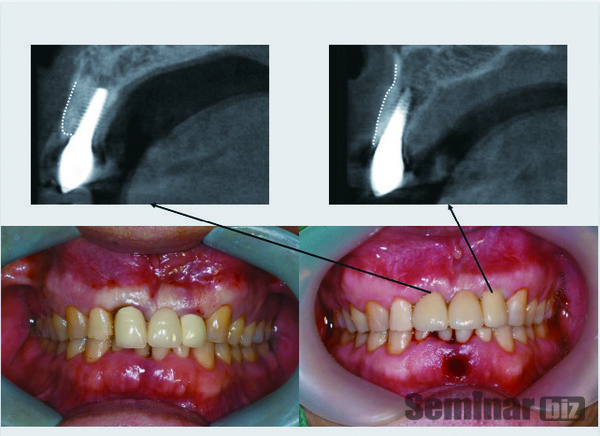

진단당일 임플란트시술에 필요한 ‘가이드’와 ‘임플란트용 임시치아’를 바로 출력할 수 있는 획기적인 기술을 보유한 회사다.

레이솔루션은 CT Impression 스캔(1단계) 을 하면 CAD 디자인(2단계)이 완성되고 3D 프린팅(3단계)이 된다. 1단계는 RAYSCAN objectscan, 2단계는 RAYDENT designer, 3단계는 RAYDENT printing의 단계를 거치게 된다.

“X레이에서 가장 중요한 것이 병소를 판단하는 능력이 아니라 계측치가 얼마나 더 정밀한 것이냐가 관건이다. 왜냐면 병소를 판단하는 것은 500정도까지 파악하면 되지만 우리가 실제로 수술할 때 가장 중요한 것은 그 길이의 정밀함이다. 레이의 CT는 0.5 mm편차에 불과하다”고 강조한다.